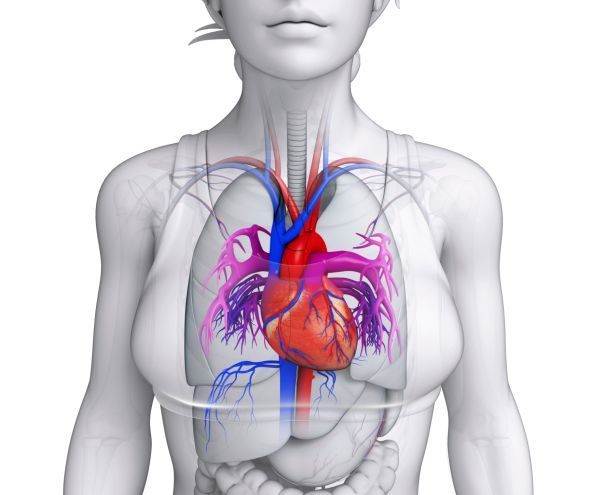

Si parla di insufficienza cardiaca quando il cuore non è più in grado di pompare abbastanza sangue ricco di ossigeno. Può manifestarsi improvvisamente, ma il più delle volte è provocata da una malattia (essenzialmente del cuore) cronica che si protrae per molto tempo. Può riguardare solo il lato destro del cuore oppure quello sinistro. Il più delle volte però coinvolge l’organo nella sua interezza. Scopriamone insieme le cause più comuni, i sintomi e cosa fare.

Quando il cuore non riesce più a svolgere regolarmente le proprie funzioni di pompaggio del sangue nelle arterie con sufficiente forza, si va creare nelle vene e nei tessuti periferici e nei polmoni un accumulo di liquidi.

Quando il cuore non riesce più a svolgere regolarmente le proprie funzioni di pompaggio del sangue nelle arterie con sufficiente forza, si va creare nelle vene e nei tessuti periferici e nei polmoni un accumulo di liquidi.

Si parla in questo caso d’insufficienza cardiaca, o scompenso cardiaco che può essere acuta, quando si manifesta a seguito di un evento improvviso o cronica se si sviluppa lentamente.